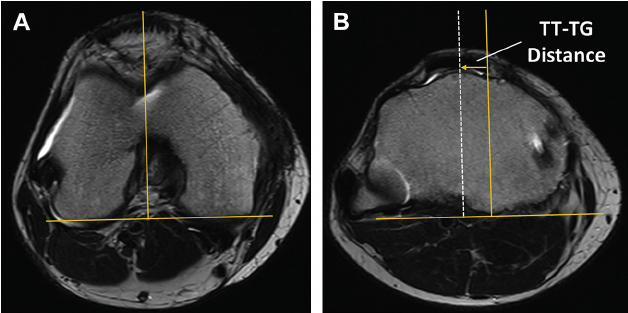

30도 flexion 한 상태에서 axial CT 를 촬영하여 TT-TG(Tibial tuberosity- trochlear groove) distance 를 측정하여 13mm 가 정상이며 20mm 이상인 경우 확실하게 비정상이 있다는 것을 확인해 볼 수 있습니다.